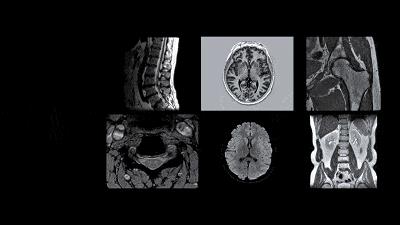

医院放射科检查通常包括三类——DR(数字化拍片机器,也就是俗称的”X光“)、CT(电子计算机体层扫描)、MRI(磁共振成像)。

MRI称得上是立体扫描,多用于椎间盘疾病,可以很好地观察软组织和椎间盘与相应的神经根,而且无放射性损伤。对于脊髓、脊柱疾患、肾、膀胱、肾上腺、妇女盆腔与生殖器官疾病、骨关节和软组织疾病等方面已被证明是最安全、方便、精确的影像学诊断方法。

2中枢神经系统

早期脑梗首选MRI,非早期脑梗或陈旧性脑梗,MRI和CT均可。

脊髓病变或脊柱病变影响到脊髓:

首选MRI,部分情况下CT辅助确诊。